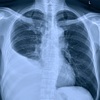

22

Q

¿Qué proyección es la siguiente?

A

PA